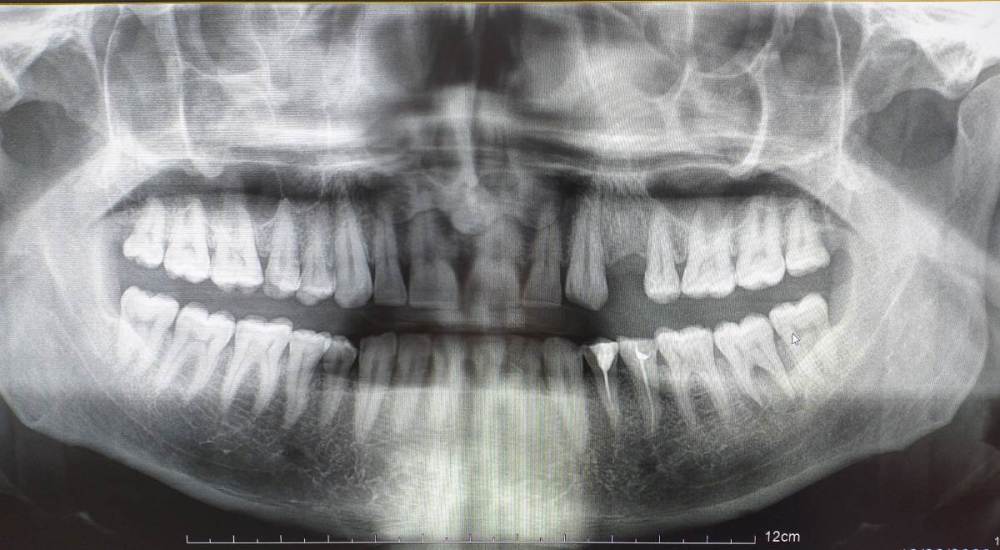

Mihail64 Опубликовано 25 декабря, 2022 Поделиться Опубликовано 25 декабря, 2022 Столкнулся с тем, что 37 зуб плохо сидит в десне (неплотное прилегание, постоянное пощипывание). Ранее при жевании были дискомфорт и несильные болевые ощущения, со временем усилились. Теперь под этим зубом на десне появился постоянно восстанавливающийся гнойник, который я удаляю и полощу хлоргексидином. Был проведен ренген, показавший, что в основаниях двух передних корней зубов были выявлены зоны воспаления. Посоветовали удалить корни и запломбировать, при этом гарантии того, что процесс не возобновится не дают, ссылаясь на переход в хроническое течение (болит более месяца). Как я понимаю сам зуб при этом цел (за ним растет еще зуб мудрости), но есть каналы по которым поступает инфекция. Прошу пояснить, правильно ли назначено лечение, можно ли оставить зуб и при этом избежать повторных абсцессов. Или лучше раз он не держится, и под ним происходит воспалительный процесс, вырвать его. Ссылка на комментарий

Mihail64 Опубликовано 26 декабря, 2022 Автор Поделиться Опубликовано 26 декабря, 2022 (изменено) Похоже перспективы не очень. Поставили также такой диагноз. Под зубом нагноение хронического характера, которое разъело костные ткани корней зуба. Сейчас образовался флюс щеки. Зуб подлежит удалению. Подскажите, ситуация именно такова? Изменено 26 декабря, 2022 пользователем Mihail64 Ссылка на комментарий

Женька Опубликовано 27 декабря, 2022 Поделиться Опубликовано 27 декабря, 2022 Возможно коллеги подскажут, что-то более конкретное. Я лично не вижу показаний к удалению по данному снимку и фото полости рта. КЛКТ возможно показало бы какие-то новые данные. По факту я вижу, что в зубе не было эндодонтии, а значит и прогнозы на излечение так называемой "кисты" очень хорошие. Просто нужен доктор, который возьмётся за лечение Как сказал выше Иван, не приговор. 1 Ссылка на комментарий

DoctorT Опубликовано 27 декабря, 2022 Поделиться Опубликовано 27 декабря, 2022 Нужно исключить трещину в зубе, если ее нет, то обычное лечение корневых каналов. P/S/ снимок конечно, как говорили коллеги КЛКТ. 1 Ссылка на комментарий